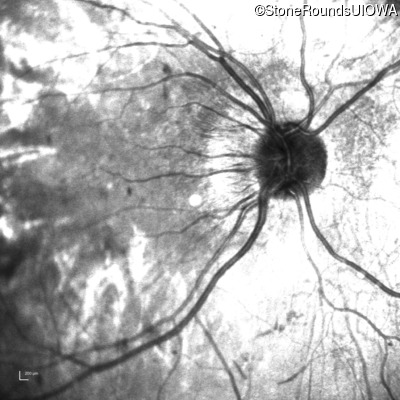

This 12 year old girl has had poor night vision and subnormal acuity since she was about 3 years old.

| Age at visit: 12 years (Visit 2) |